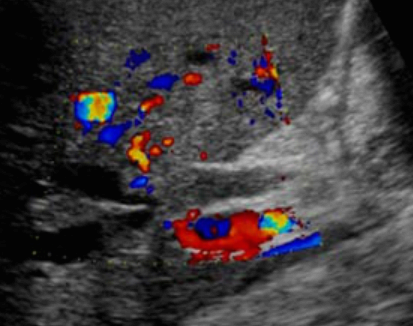

Choledocholithiasis US finding

- 총담관 내에 후방음향음영을 동반한 강한 에코가 관찰된다.

- 총담관의 확장 소견이 보인다. ( 7mm 이상)

- 담석이 관찰되지 않고 간외, 간내담관의 확장소견을 시사하는 엽총징후(shotgun sign)이나 평행관 징후(parallel channel sign)가 관찰되기도 한다.

- 엽총징후(shotgun sign): 간외 담관이 확장되어 간외 담관과 문맥이 이웃해 관찰된다.

- 평행관 징후(parallel channel sign): 간내 담관이 확장되어 인접하고 있는 문맥과 나란히 2개의 관상구조로 나타난다.